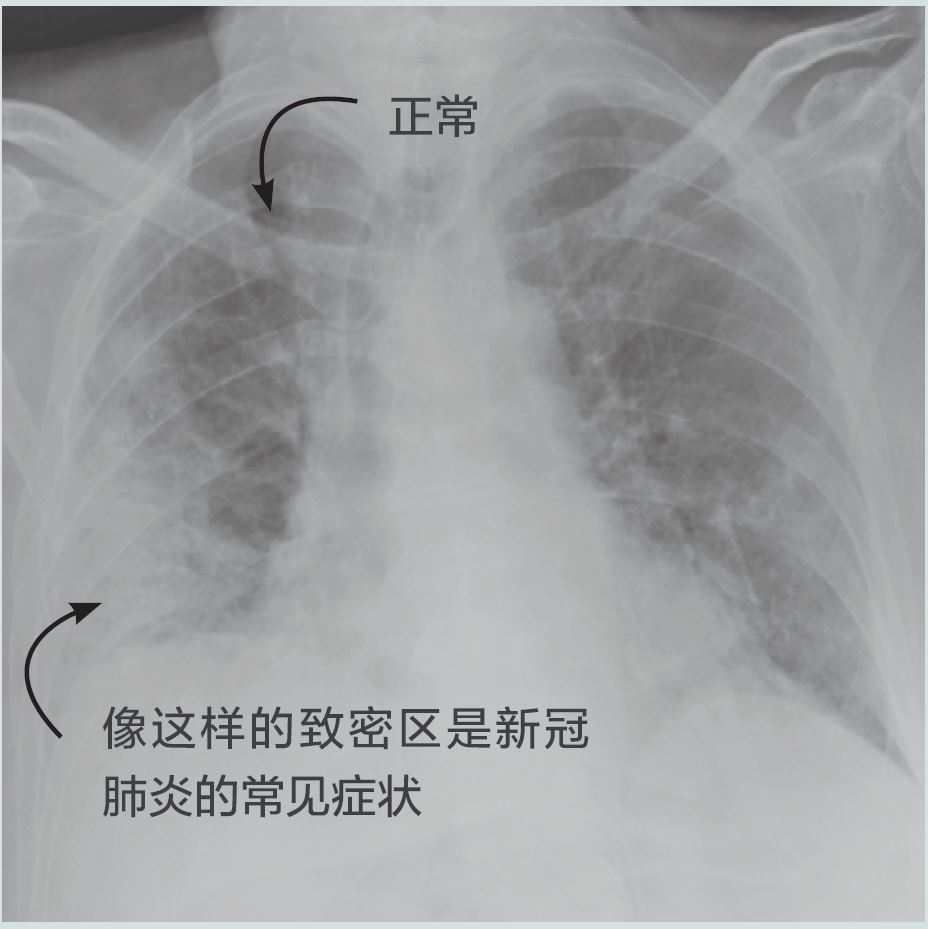

imaging-chinese-1.jpg

新冠肺炎患者的胸部X光片。兩個肺都有征兆,尤其是右肺。(圖/博洛尼亞大學醫院管理局圣奧爾索拉-馬爾皮吉綜合醫院核醫學科L. Zanoni)

X光是一種射線。許多人最熟悉的是它們用于診斷骨折或檢查牙齒。

衛生保健專業人員可以使用X光機來利用X射線。將患者安置在機器前,使精心選定的X射線劑量穿過身體靶區。身體較厚實、較密集部位(如骨骼)穿過的X射線較少,而較柔軟、較單薄部位穿過的X射線較多。X射線從身體的另一側穿出時,利用專用探測器捕捉它們的圖案,形成身體內部結構及其變化的圖像。

為評估新冠肺炎,可進行人體胸部X光檢查,查看肺部組織情況。這適用于有新冠肺炎呼吸道癥狀的患者。X光檢查還可用于監測疾病變化以及做出治療和后續決定,例如是否讓患者住院或將癥狀嚴重的患者送去做CT掃描。

“由于X光機在醫療中心通常隨時可用,許多衛生保健專業人員已經可以使用這些工具幫助他們的國家應對新冠肺炎。”Pellet說,“一些X光機也比較輕便、輕巧,并且易于操作和去污,這在疫情中至關重要,特別是在醫療分診區或臨時醫院環境中。”